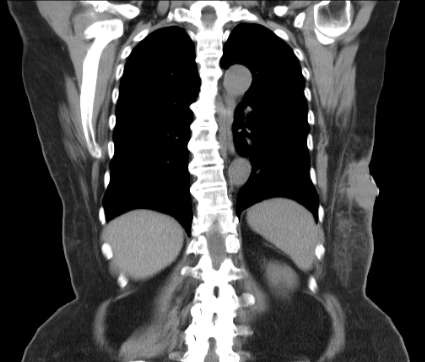

病例1: 60岁局部胸壁复发和活动性出血

60 y/o local and chest wall recurrence and lymph node metastases

CT 冠状位扫描 |